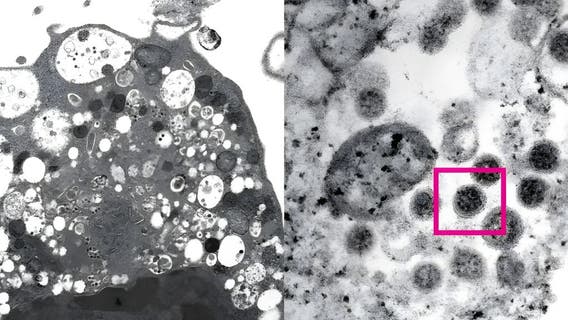

Boston University researchers claim to have developed new, more lethal COVID strain in lab

Researchers at Boston University added a spike protein from the Omicron variant with the original Wuhan strain, which has an 80% kill rate